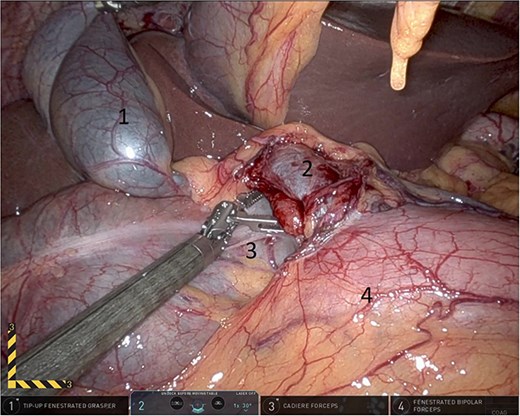

Upon entering the abdominal cavity, dilated bowel loops were observed (Fig. 2), and a significant portion of the colon was found herniated through the foramen of Winslow (Fig. 3). The herniated colon was covered by the pars flaccida (Fig. 4) (Video S1). Careful dissection was performed anterior to the hepatoduodenal ligament (Fig. 5). The gall bladder was retracted to the patient's right upper quadrant, which allowed for the retraction of the foramen of Winslow (Fig. 6) (Video S1). After carefully placing the tip of the instrument posterior to the portal vein and gently elevating it, the herniated colon was successfully reduced (Fig. 7) (Video S1).

Gallbladder was retracted to the patient's right upper quadrant which allowed for the retraction of the foramen of Winslow and anterior mobilization of it (1: gall bladder, 2: herniating colon, 3: first part of the duodenum, 4: portal vein).

Elevating hepato-duodenal ligament structures to allow reduction of herniating colon (1: gall bladder, 2: portal vein, 3: herniating colon, 4: first part of the duodenum).